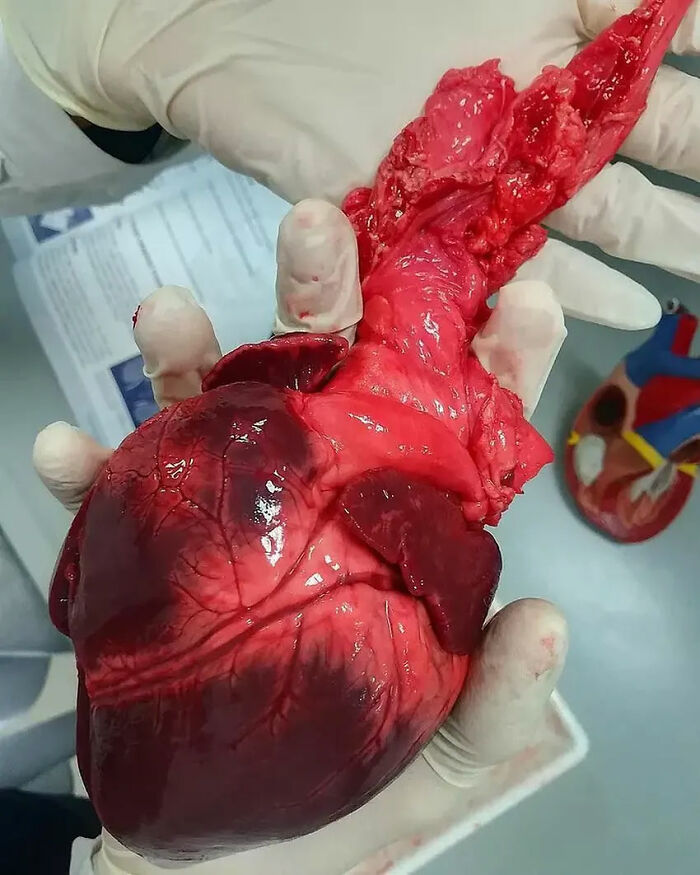

Pediatric Heart Transplantation

A Mega-Size Globular Heart!! This Very Large Heart Has A Globoid Shape Because All Of The Chambers Are Dilated. It Felt Very Flabby, And The Myocardium Was Poorly Contractile